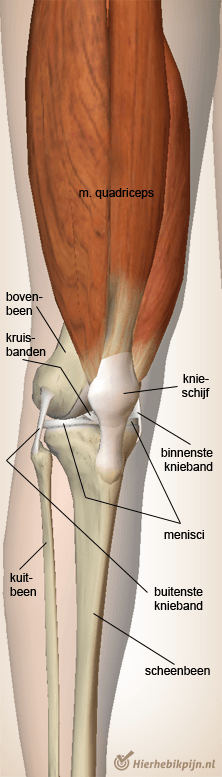

Knie